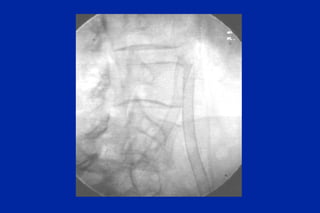

Este documento resume los principales tipos y técnicas de angiografía. Describe brevemente la angiografía, arteriografía, flebografía y linfografía, así como las técnicas de contraste y materiales utilizados. También explica los principales accesos vasculares, la técnica de Seldinger, la angiografía por sustracción digital y algunas técnicas endovasculares comunes.